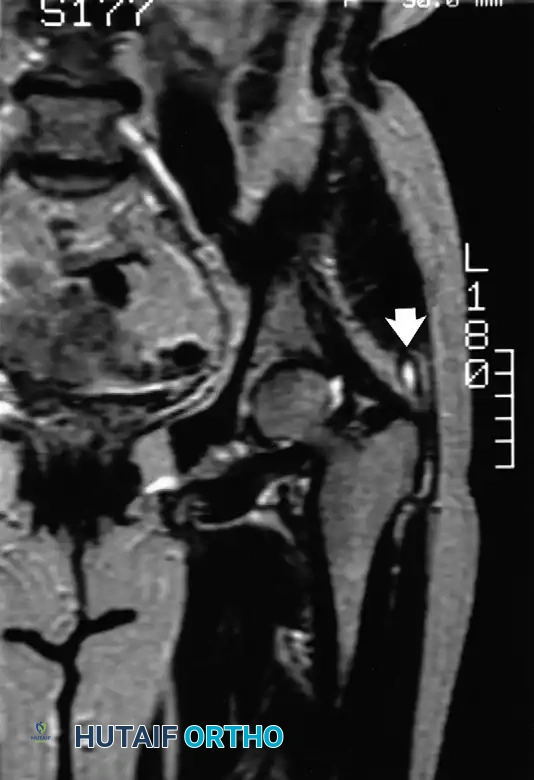

Popliteal Cyst (Baker's Cyst)

Originally described by Adams in 1840 and later popularized by Baker in 1877, a popliteal cyst is typically a distension of the gastrocnemio-semimembranosus bursa. This bursa naturally communicates with the knee joint in a significant percentage of the population.

Pathogenesis:

Meyerding and Van Demark established that these cysts arise either from direct herniation of the posterior synovial capsule or, more commonly, via a one-way valve mechanism allowing synovial fluid to escape from the knee joint into the bursa during flexion, preventing its return.

Pediatric vs. Adult Presentations:

Touloukian and Malloch highlighted critical differences in management based on patient age:

* Children: The cyst rarely communicates with the joint, and intra-articular pathology is exceptionally rare. The vast majority resolve spontaneously with benign neglect. Surgical excision is reserved for massive, symptomatic cysts causing neurovascular compression.

* Adults: Popliteal cysts in adults are almost universally (98%) secondary to intra-articular pathology, most commonly posterior horn medial meniscus tears or advanced osteoarthritis.

Surgical Management in Adults:

Treating the cyst without addressing the intra-articular pathology guarantees recurrence. Management should focus on arthroscopic debridement or repair of the offending meniscal tear and management of chondral defects. The cyst itself rarely requires open posterior excision unless it is massive, multiloculated, or causing compressive neuropathy of the tibial nerve. If open excision is performed, the stalk communicating with the joint capsule must be meticulously dissected, ligated, and the capsular defect closed to prevent synovial fluid extravasation.